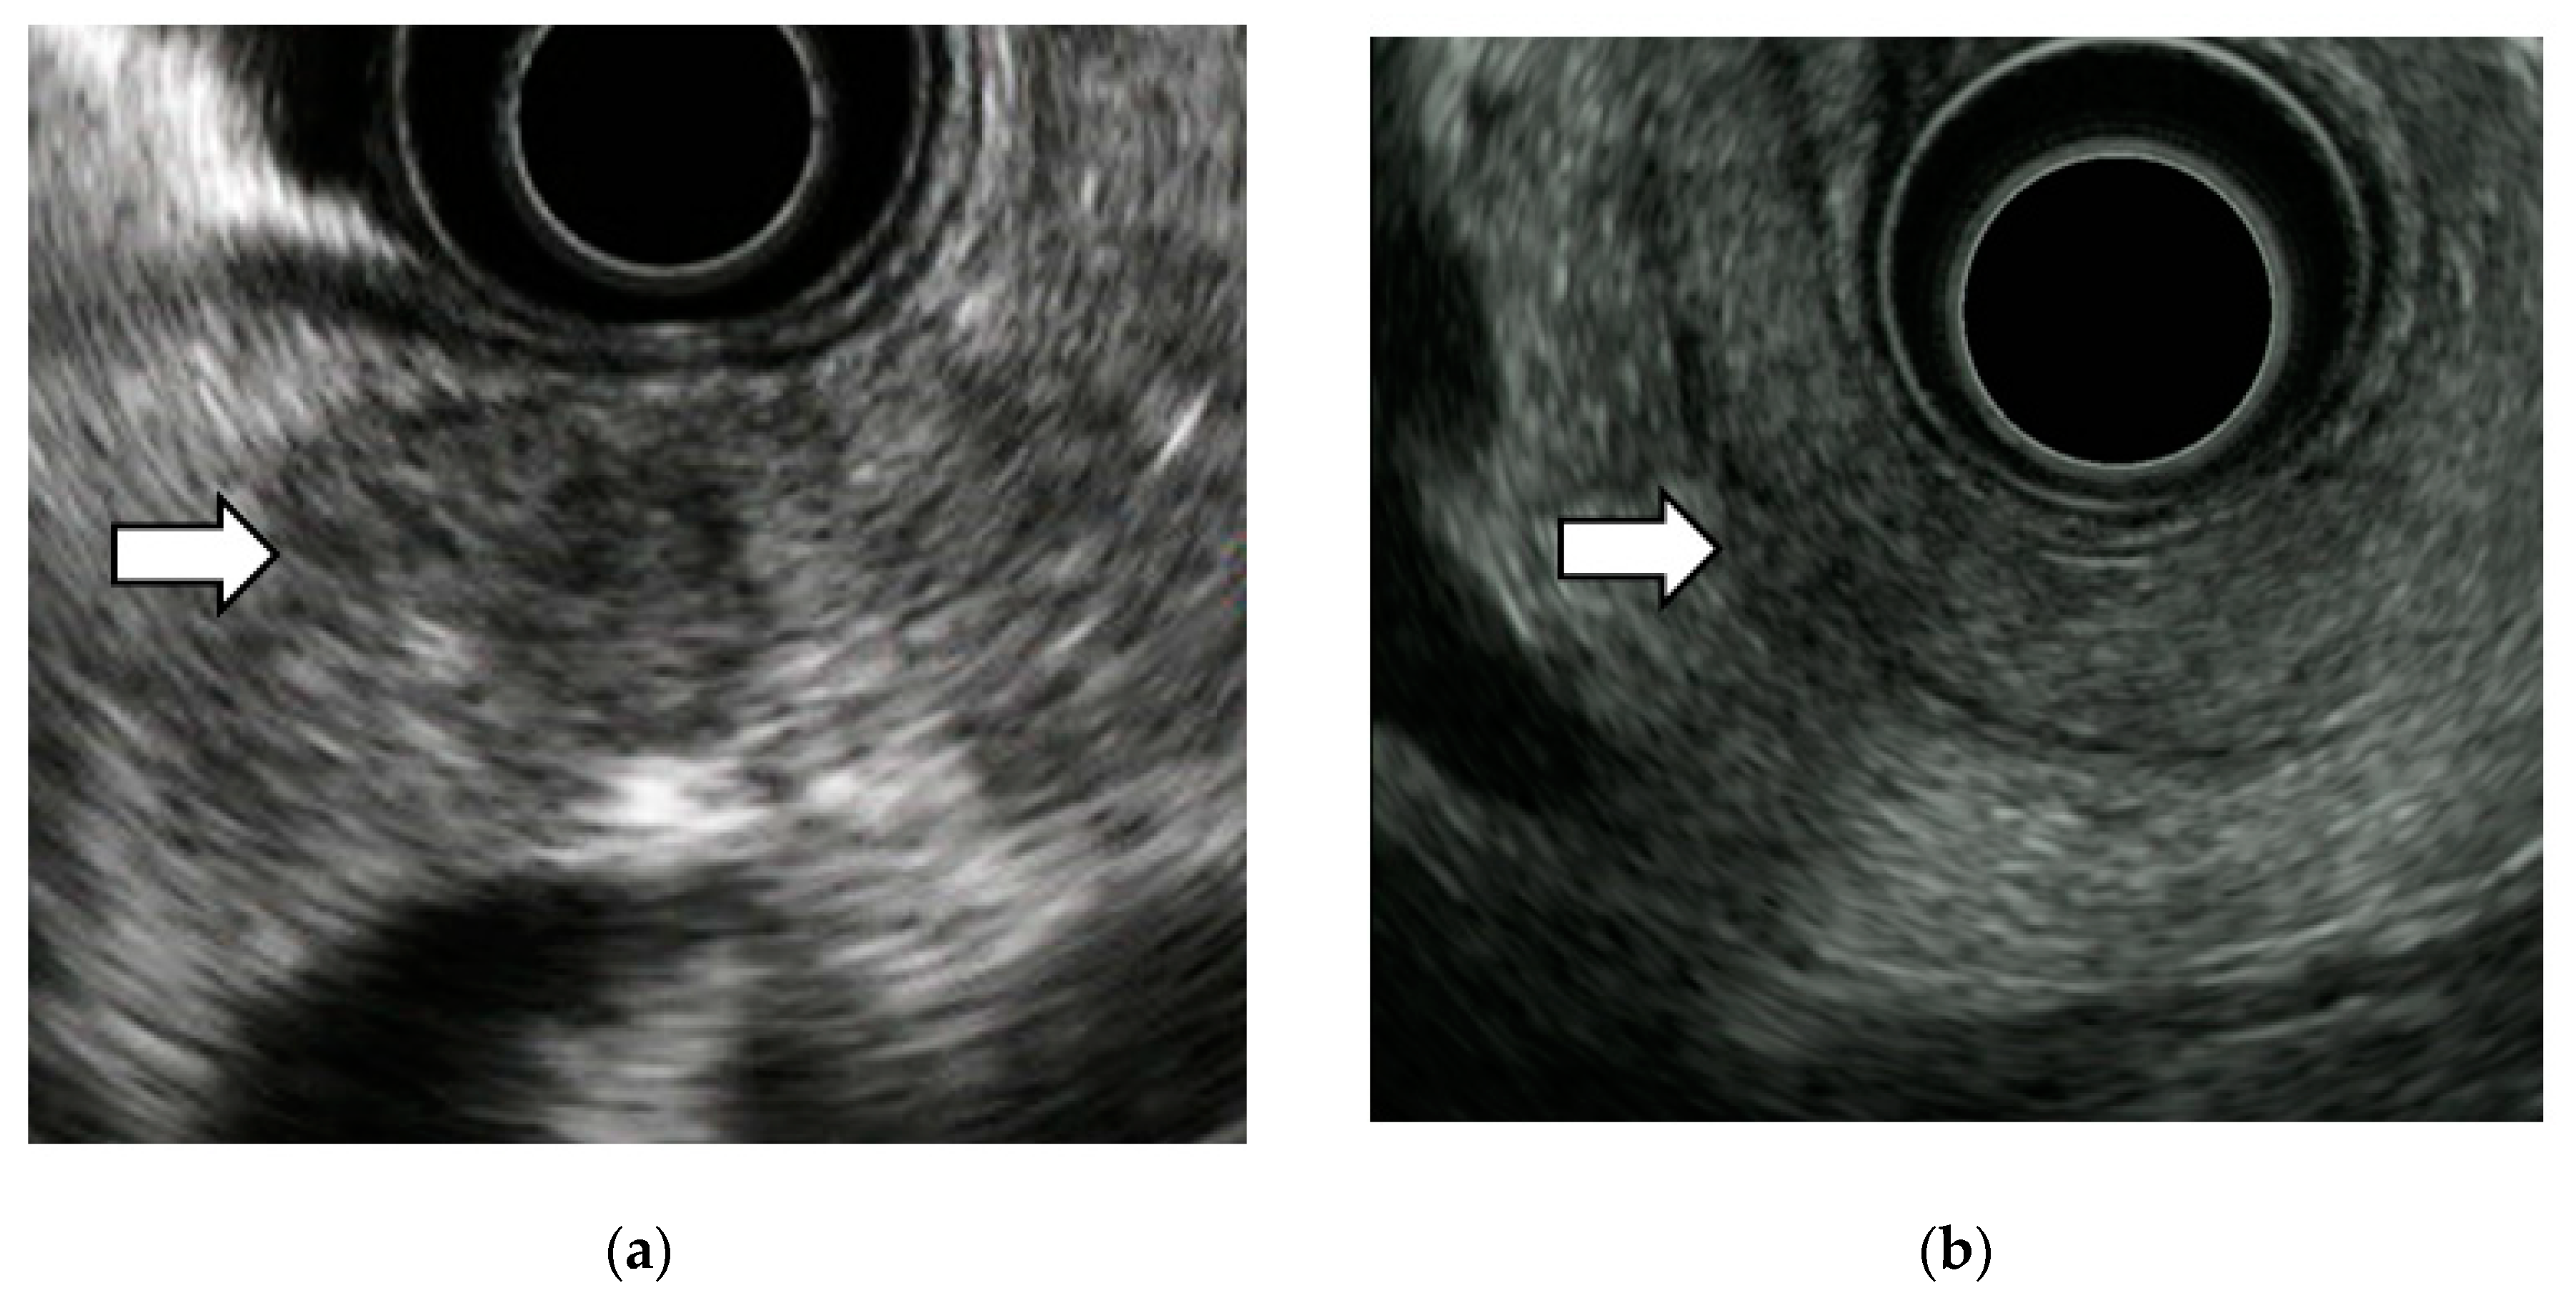

3.2. EUS Imaging Findings of Stage 0 PC

- Izumi, Y.; Hanada, K.; Okazaki, A.; Minami, T.; Hirano, N.; Ikemoto, J.; Kanemitsu, K.; Nakadoi, K.; Shishido, T.; Katamura, Y.; et al. Endoscopic ultrasound findings and pathological features of pancreatic carcinoma in situ. Endosc. Int. Open. 2019, 7, E585–E593. [Google Scholar] [CrossRef]